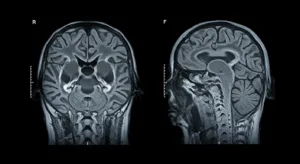

Look at this picture. It shows how PET and MRI use different ideas from physics to make treatments. They help doctors make good plans to treat cancer.

2. Magnetic resonance imaging (MRI) Scans

Magnetic resonance imaging is a procedure to make pictures of the inside of our body. It does not use X-rays; although, it relies on magnets and radio waves. Our body is mostly made of water and water has small parts like magnets. The big magnet on the MRI machine makes these small parts line up in a single direction. Then, the machine transmits radio waves that send these small parts. When they return to their original position, they emit their own radio signals.

The MRI machine hears such signals. One body part will report back different from another body part. This makes the machine draw a clear picture. Doctors can view tumors in position and watch how water and blood flow from it, thus knowing the tumor better. The pictures are changing with a slider for you to see. When the radio waves are altered, the picture looks changed, and it allows the doctors to see more about the tumor. Such imaging techniques are of great help in treatment plans. It is all diagnostic radiology.